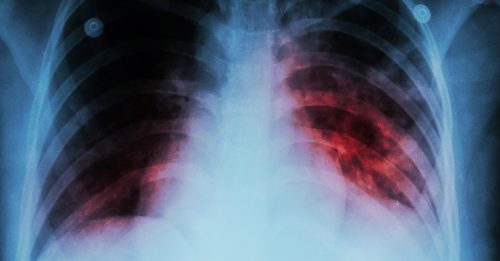

结核病

针刺伤 结核病 听力损失 卫长揭去年 5617起医护事故

丹州7个月636宗 结核病夺35人命

去年通报2.6万结核病例 夺2580人性命

结核病再度成为 全球头号传染病杀手